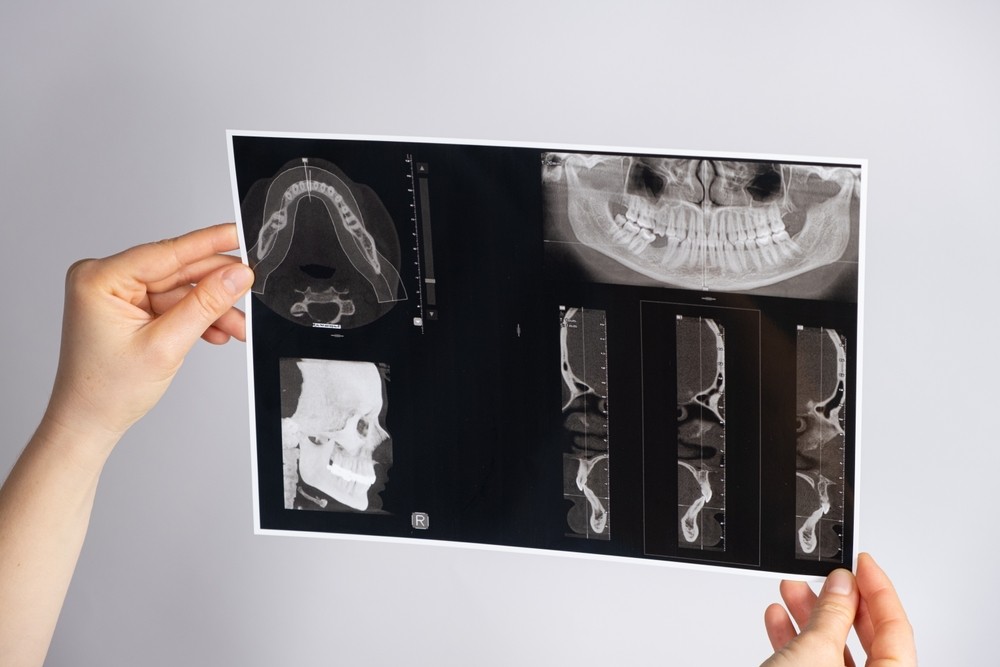

Tomografiile dentare moderne sunt tehnologii de imagistică medicală avansate care utilizează raze X pentru a crea o imagine tridimensională a structurilor interne ale dinților și maxilarelor. Această metodă de imagistică dentară este utilizată în principal pentru a detecta problemele dentare care nu pot fi observate cu ajutorul altor tehnologii de imagistică dentară, precum radiografiile dentare obișnuite. Tomografiile dentare moderne permit medicilor stomatologi să observe în detaliu structurile osoase, incluzând nervii, vasele de sânge și țesuturile moi din jurul dinților.

Tomografia dentară 3D, sau tomografia dentară cu fascicul conic de raze X (CBCT), este o tehnologie de imagistică medicală care folosește un fascicul conic de raze X pentru a crea o imagine 3D a structurii dentare și a maxilarelor. Această metodă de imagistică dentară este utilizată pentru a detecta problemele dentare și maxilare, precum:

CBCT este o tehnologie avansată de imagistică dentară, oferind o imagine tridimensională extrem de precisă a structurilor interne ale dinților și maxilarelor. Imaginile obținute cu ajutorul acestei tehnologii pot fi vizualizate de pe orice computer și sunt extrem de utile pentru medicul stomatolog în diagnosticarea afecțiunilor dentare și maxilare și planificarea tratamentelor dentare complexe.

Tomografia dentară digitală (CT) este o tehnologie de imagistică medicală care utilizează raze X pentru a crea imagini transversale ale dinților și maxilarelor. Această metodă de imagistică dentară este utilizată pentru a detecta problemele dentare și maxilare, precum:

Tomografia dentară digitală este una dintre cele mai utilizate metode de imagistică dentară, datorită faptului că este mai puțin invazivă decât alte tehnologii de imagistică dentară și oferă imagini detaliate ale structurilor interne ale dinților și maxilarelor.

Pentru a interpreta imaginile dentare rezultate din tomografiile dentare, este necesară experiență și cunoștințe în domeniul imagisticii dentare. Medicul stomatolog sau radiologul va examina imaginile pentru a determina afecțiunile și problemele dentare și maxilare. Medicul stomatolog poate discuta cu pacientul despre rezultatele tomografiei și poate planifica tratamentul adecvat, în funcție de diagnostic.